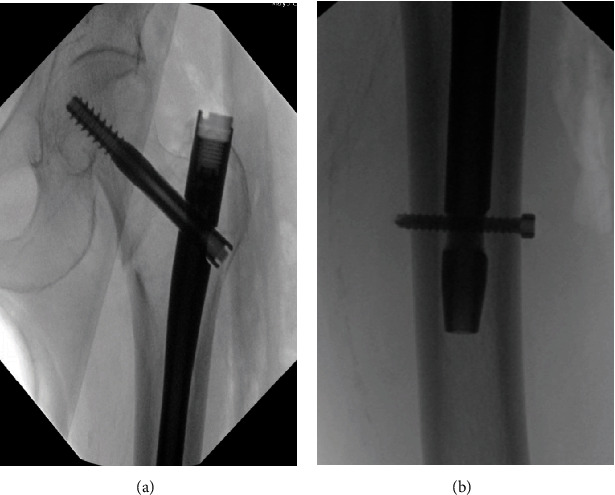

介绍:髋关节转子间骨折的手术治疗是一种常见手术,术中并发症发生率较低。在不切开复位的情况下放置髓内钉,血管损伤非常罕见。在髋部骨折闭合复位和髓内钉置入术后,远端联锁螺钉水平出现直接动脉损伤和活动性出血的病例极少见。我们报告了一例这样的病例。病例介绍:一名 88 岁的女性因左侧转子间髋部骨折到急诊科就诊。按计划对左侧髋部骨折进行了闭合复位并用头髓内钉固定,术中没有出现任何明显的技术问题。术中患者病情保持稳定。无需进行切开复位。术后,患者出现失血性休克,需要大量输血。血管造影显示,髓内钉远端锁定螺钉处出现肌肉内血肿,并伴有活动性外渗。患者随后需要进行栓塞治疗。术后九天,她开始服用伊利奎斯(Eliquis)预防深静脉血栓形成,目前已能独立行走,血肿也有消退迹象。讨论股深动脉损伤可能源于手术过程中的各种机制。动脉粥样硬化会使患者因血管僵硬而面临更高的并发症风险。在本病例中,钻孔超出股内侧皮质被认为是导致动脉损伤的原因。结论:在手术过程中应注意防止钻头陷入股内侧皮质之外。谨慎观察患者的生命体征和临床病程可及早发现血管并发症。

Introduction: Surgical management of intertrochanteric hip fractures is a common surgery with low rates of intraoperative complications. Vascular injuries are exceptionally rare when placing an intramedullary nail without open reduction. There are very few reported cases of direct arterial injury and active bleed at the level of the distal interlocking screw following closed reduction and intramedullary nailing of a hip fracture. We report one such case. Case Presentation: An 88-year-old female presented to the emergency department with a left intertrochanteric hip fracture. Closed reduction with a cephalomedullary nail fixation of the left hip fracture occurred as planned without any obvious intraoperative technical issues. The patient remained stable intraoperatively. No open reduction was required. Postoperatively, the patient developed hemorrhagic shock and required massive transfusion protocol. Angiography demonstrated an intramuscular hematoma at the level of the distal intramedullary nail interlocking screw with active extravasation. The patient subsequently required embolization. Nine days following surgery, she began Eliquis for DVT prophylaxis and was ambulating independently with signs of hematoma resolution. Discussion: Profunda femoris artery injury can stem from various mechanisms during surgery. Atherosclerosis places patients at a higher risk of complication due to rigid vessels. In this case, it is believed that drilling beyond the medial femoral cortex led to the arterial injury. Conclusion: Care should be taken to prevent drills from plunging beyond the medial femoral cortex during surgery. Cautious observation of patient's vitals and clinical course can allow for early detection of vascular complication.